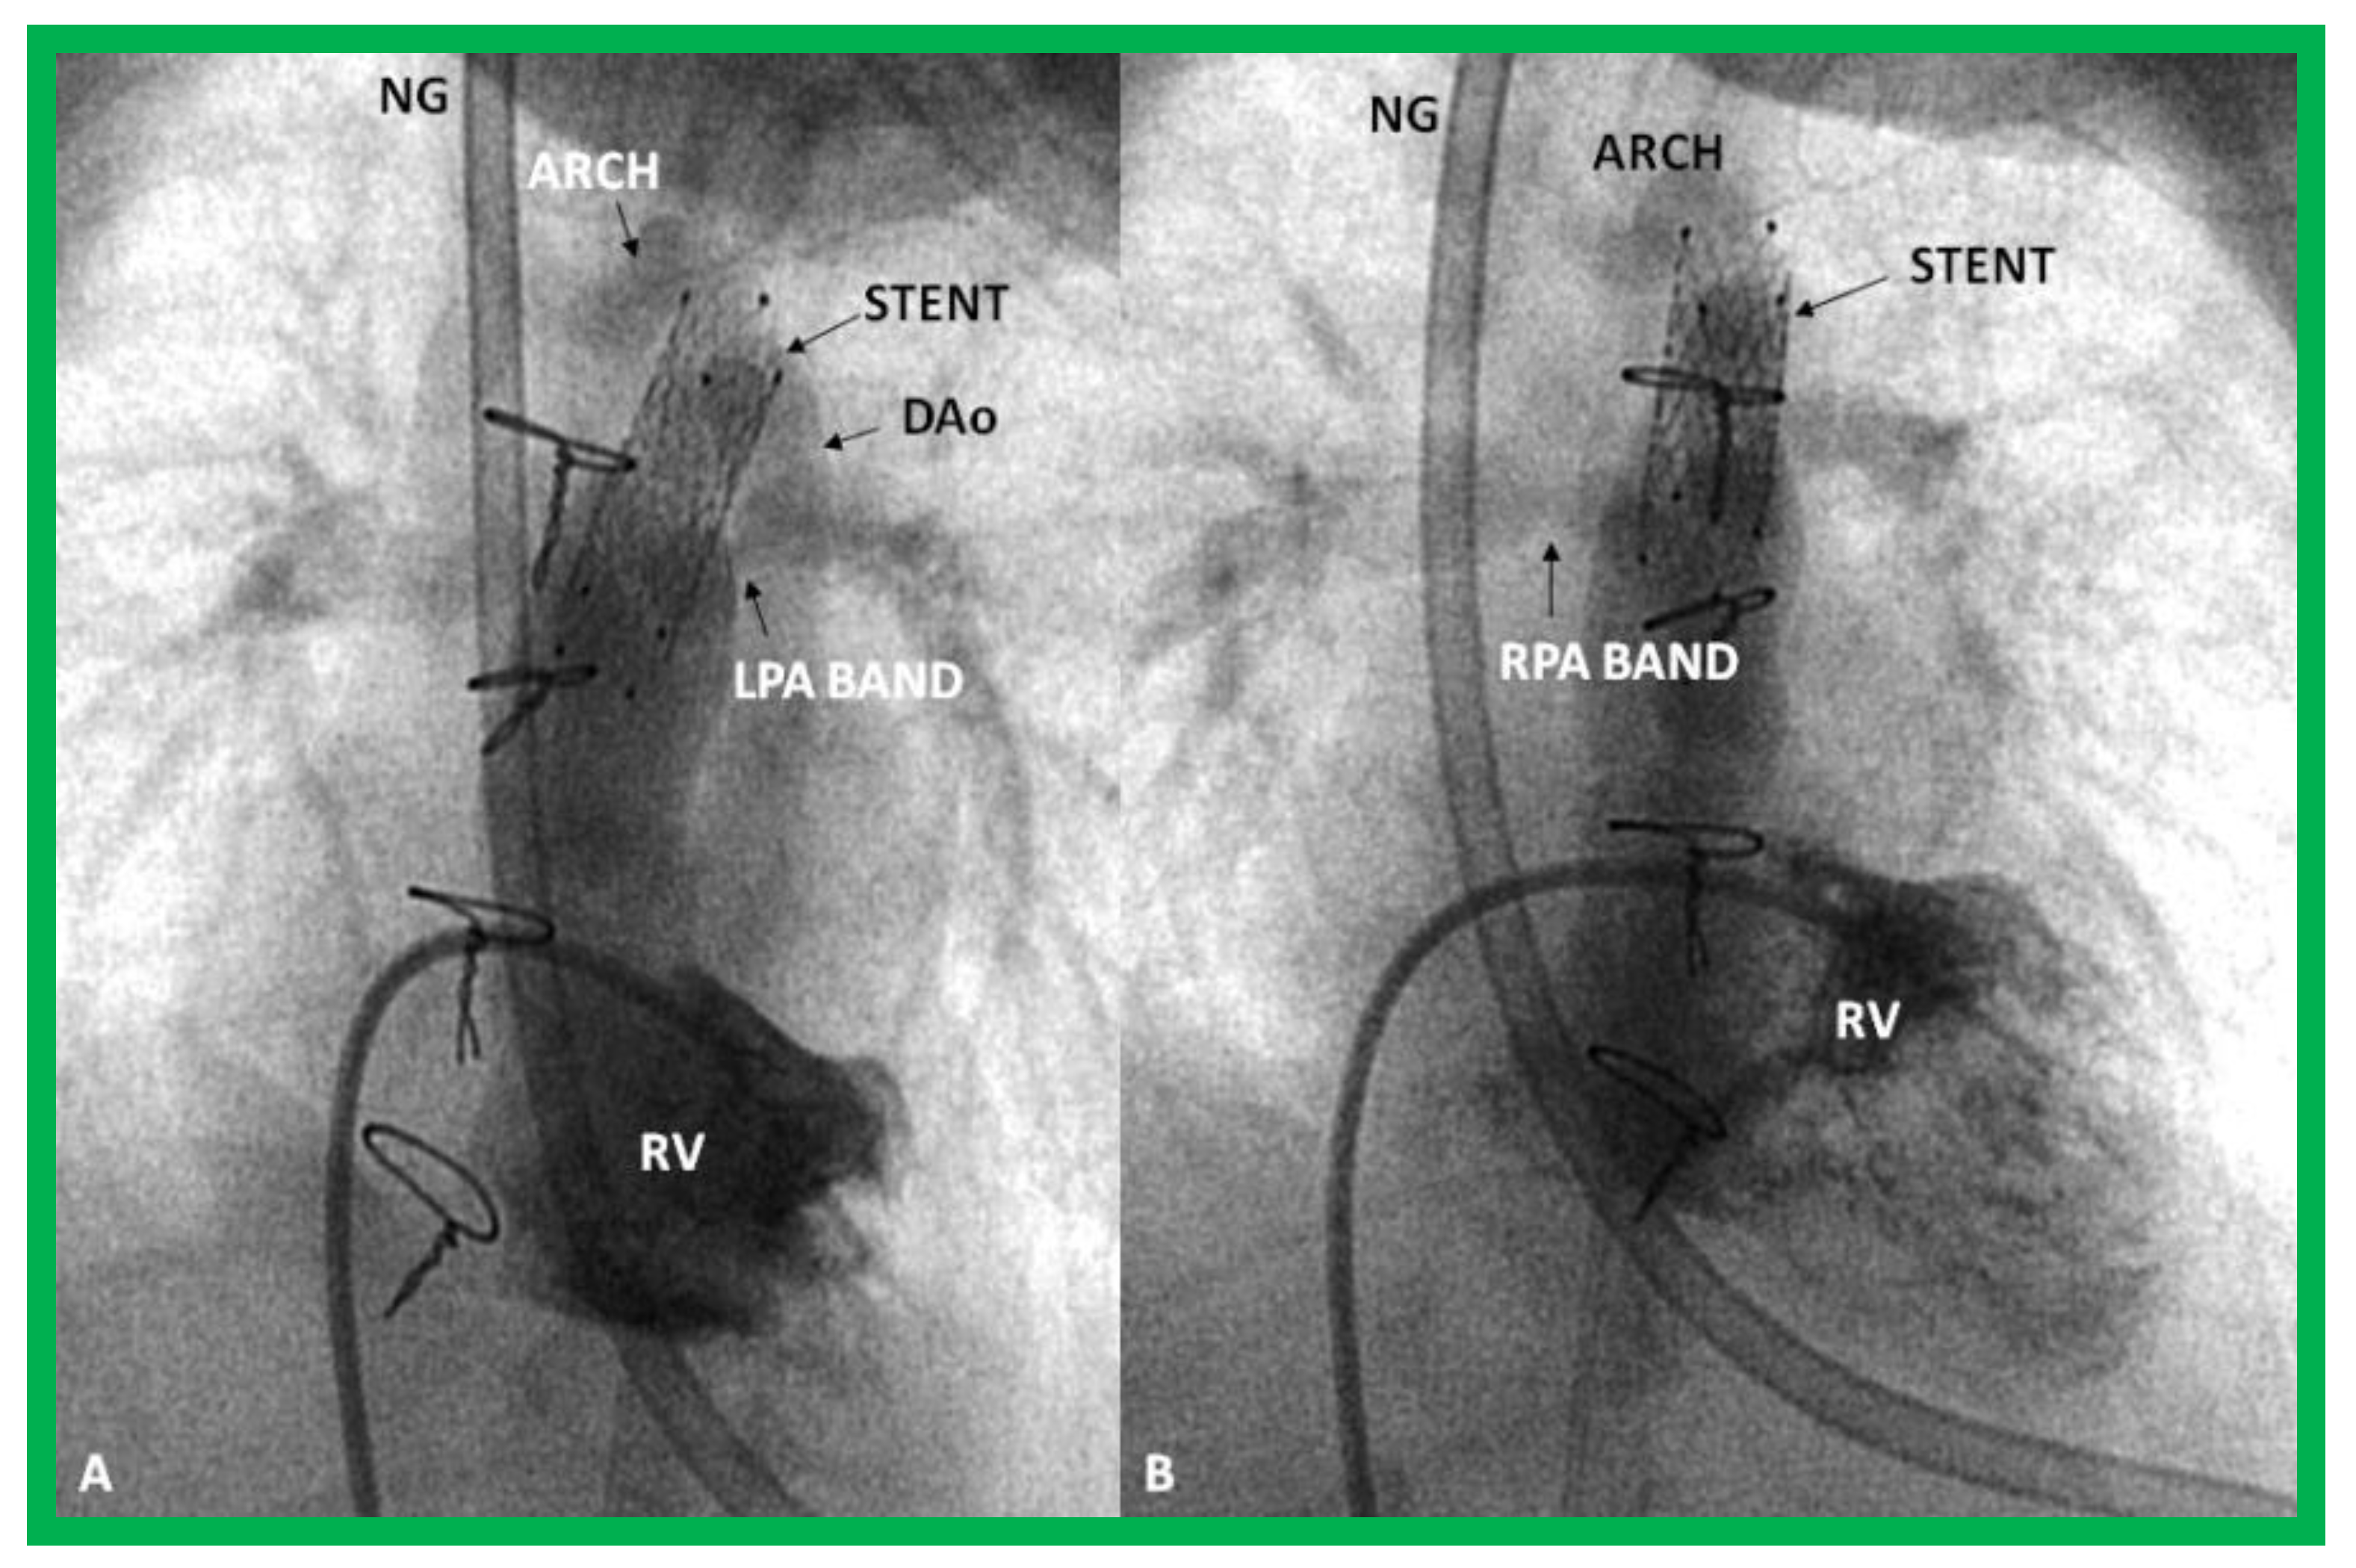

- Akintuerk, H.; Michel-Behnke, I.; Valeske, K.; Mueller, M.; Thul, J.; Bauer, J.; Hagel, K.; Kreuder, J.; Vogt, P.; Schranz, D. Stenting of the arterial duct and banding of the pulmonary arteries: Basis for combined Norwood stage I and II repair in hypoplastic left heart. Circulation 2002, 105, 1099–1103. [Google Scholar] [CrossRef] [PubMed]

- Galantowicz, M.; Cheatham, J.P. Lessons learned from the development of a new hybrid strategy for the management of hypoplastic left heart syndrome. Pediatr. Cardiol. 2005, 26, 190–199. [Google Scholar] [CrossRef] [PubMed]

- Photiadis, J.; Sinzobahamvya, N.; Hraška, V.; Asfour, B. Does bilateral pulmonary banding in comparison to Norwood procedure improve outcome in neonates with hypoplastic left heart syndrome beyond second-stage palliation? A review of the current literature. J. Thorac. Cardiovasc. Surg. 2012, 60, 181–188. [Google Scholar] [CrossRef] [PubMed]